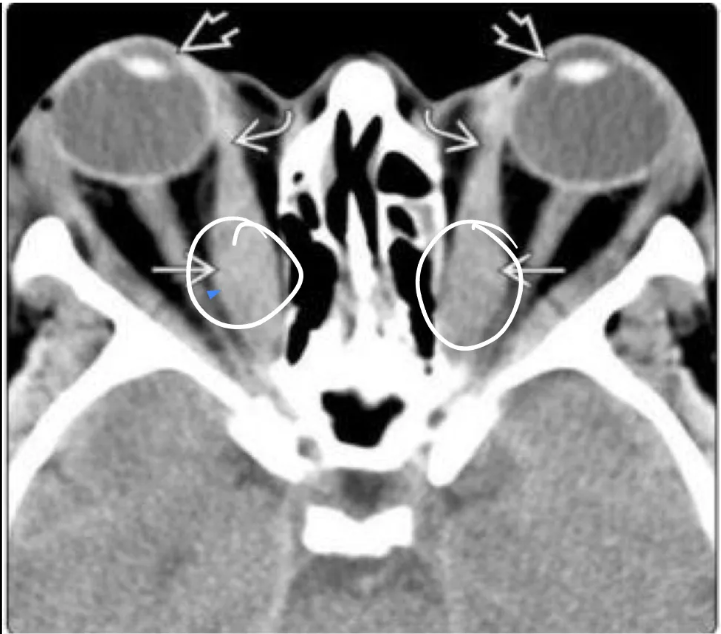

qué esperas ver en una TC por exoftalmos

protrusión ocular anormal, Disociación índice globo ocular-línea intercigomática (Si línea no cruza los ojos es anormal)

Qué esperas ver en una RM de exoftalmos

Protusion ocular anormal, Disociación índice ocular-línea intercantal y Masas ocupativas retroocular

Clave en imagen para diagnosticar la orbitopatía tiroidea

Agrandamiento BILATERAL de los músculos extraoculares

Hallazgos que podemos encontrar en una TC de orbitopatía tiroidea

Agrandamiento de los músculos extraoculares

Áreas de baja densidad debido a depósitos de glucosaminoglicano

Exoftalmos

Nervio óptico estirado